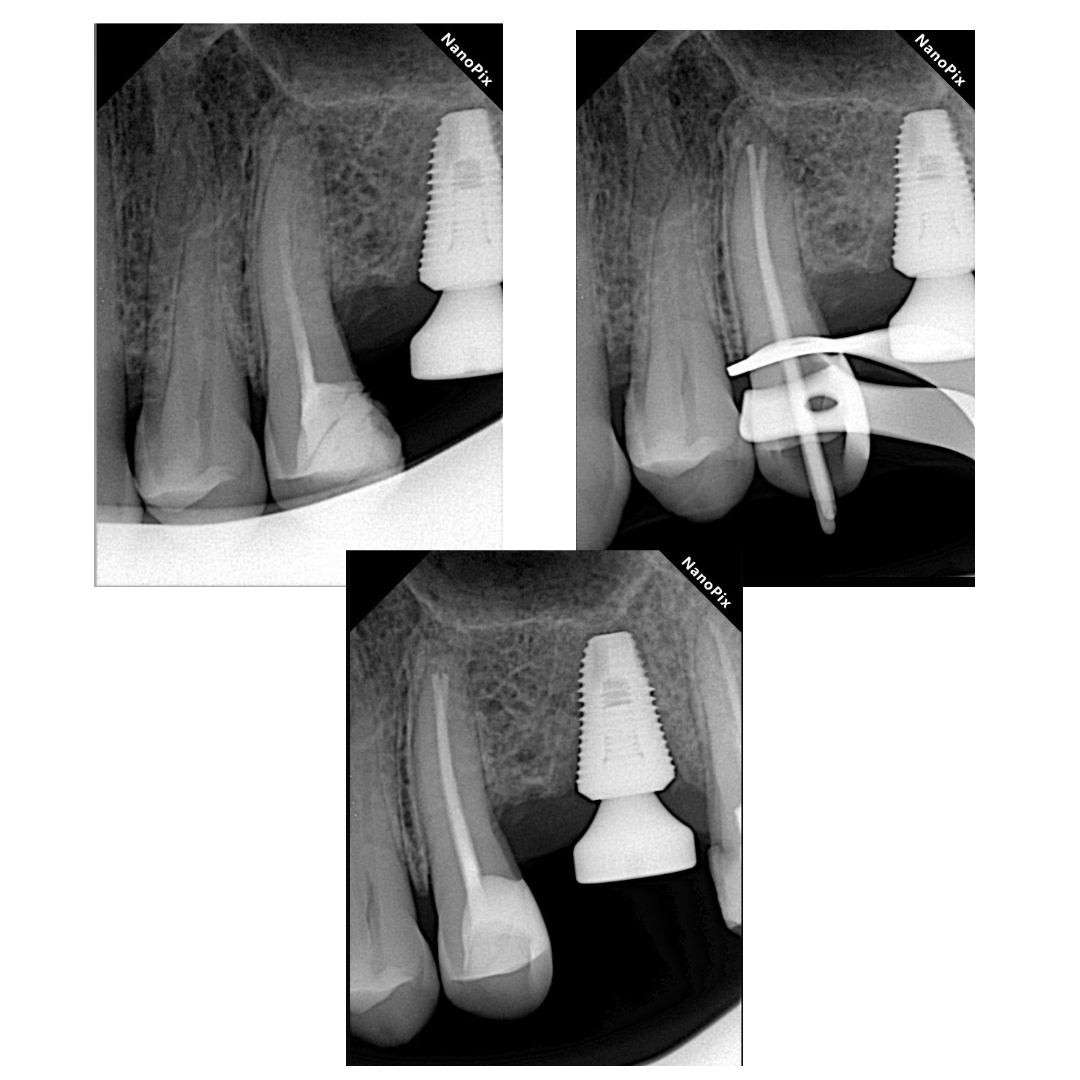

2. 10 к-файлом мануально чувствуется констрикция и/или показания апекс локатора близки к «красной черте»:

-Измеряю эту длину

-Делаю Rvg с 10 к-файлом для подтверждения

-Принимаю эту длину за рабочую